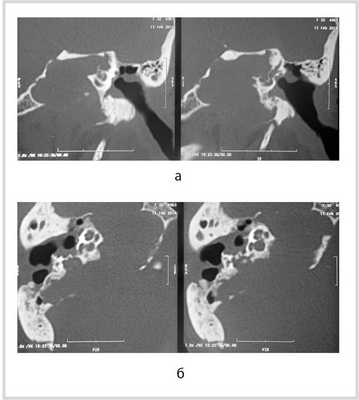

Результаты: МСКТ височной кости с достаточной точностью и специфичностью выявляет различные деструктивные процессы, что важно для определения границы распространения образования и соответственно соотнесения данных границ c классификацией холестеатомы пирамиды височной кости. На основании КТ-снимков и обновленной классификации холестеатомы пирамиды височной кости Moffat - Smith образования были распределены в зависимости от локализации по отношению к лабиринту на супралабиринтную (n - 9), супралабиринтную-апикальную (n - 3), инфралабиринтную (n - 3), инфралабиринтную-апикальную (n - 5), массивную лабиринтную (n - 1) и массивную лабиринтную с апикальным распространением (n - 1). Таким образом, в данной статье мы попытались описать границы типов холестеатом пирамиды височной кости на основании МСКТ височных костей.

Results: MSCT of the temporal bone reveals various destructive processes with high accuracy and specificity, that is important for determining the boundaries of the tumor and thus the classification of the petrous pyramid cholesteatoma. Based on CT images and updated Moffat-Smith petrous pyramid cholesteatoma classification, depending on the location in relation to the labyrinth the tumors were distributed on the supra-labyrinth (n-9), supra-labyrinth-apical (n-3), infra-labyrinth (n-3), infra-labyrinth-apical (n-5), massive labyrinth (n-1) and massive labyrinth petrous pyramid cholesteatoma with apical proliferation (n-1). Thus, in this article we have attempted to describe the boundaries of various types of the petrous pyramid cholesteatoma on the basis of the MSCT of the temporal bones.

На основании детального анализа МСКТ височной кости, обзора современной литературы, а также опыта хирургического лечения данной патологии нами детализирована классификация холестеатомы пирамиды височной кости (табл. 1).

Рис. 1. КТ височных костей пациентки М. а — коронарная проекция: деструктивная полость в пирамиде височной кости, заполненная субстратом неоднородной плотности, капсула лабиринта значительно разрушена на уровне базального и апикального завитков улитки, латерального и верхнего полукружных каналов; б — аксиальная проекция: деструктивная полость с разрушением задней грани пирамиды, передневерхней и нижней поверхности.